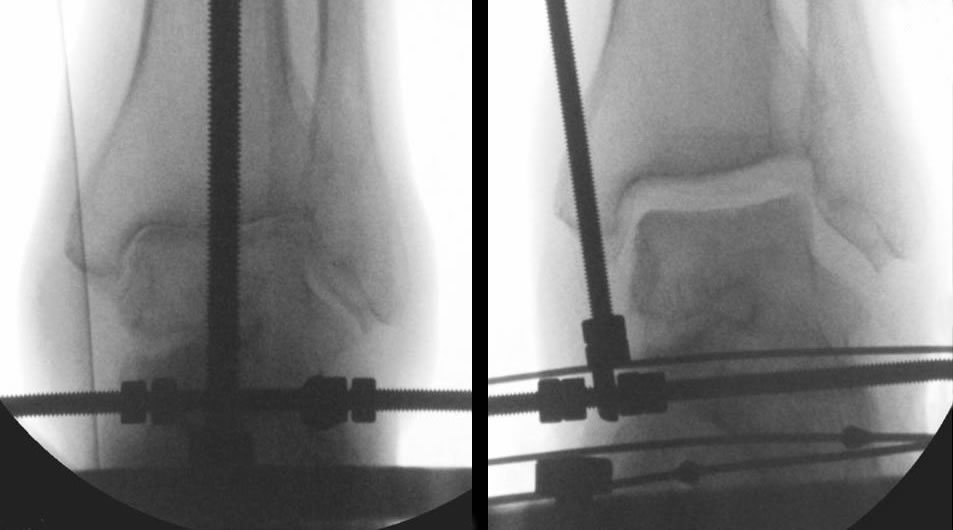

What is ankle distraction????

This was popular about 3-4 years ago. An external fixator was applied to the ankle to stretch out the ankle joint and relieve pressure on the joint to stimulate healing. By itself the procedure does NOT have long lasting results that we have found. But - when used with the procedures explained above it may have some promising results. Look at photo below. on the left is a severely arthritic ankle with no joint space on the xray- this is a very bad sign. On the right is an xray of the same ankle during distraction, the joint is literally pulled apart for 6 to 8 weeks and this helps it to heal. Again this is a procedure for very select cases.